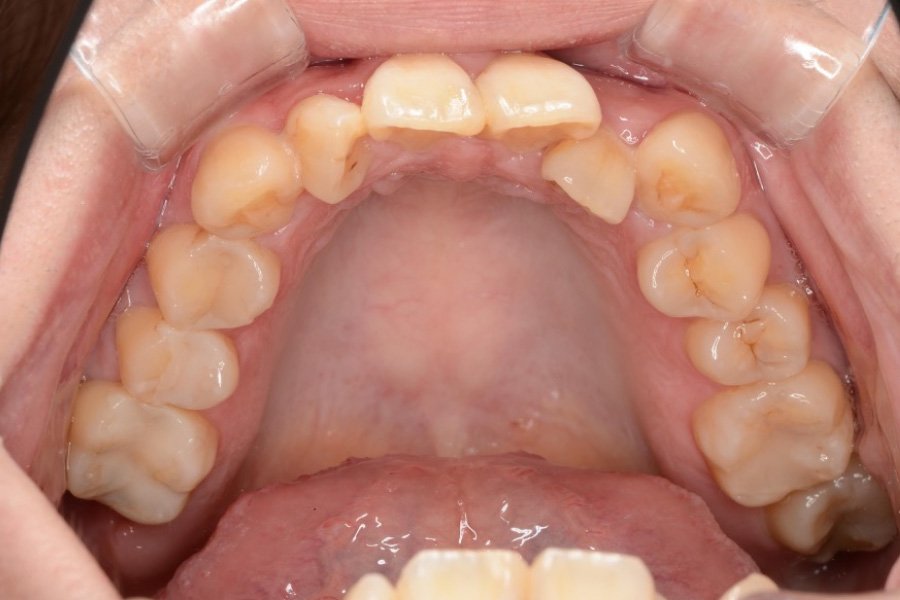

治療前

主訴 全体のガタつきが気になる

治療内容 インビザライン矯正

非抜歯